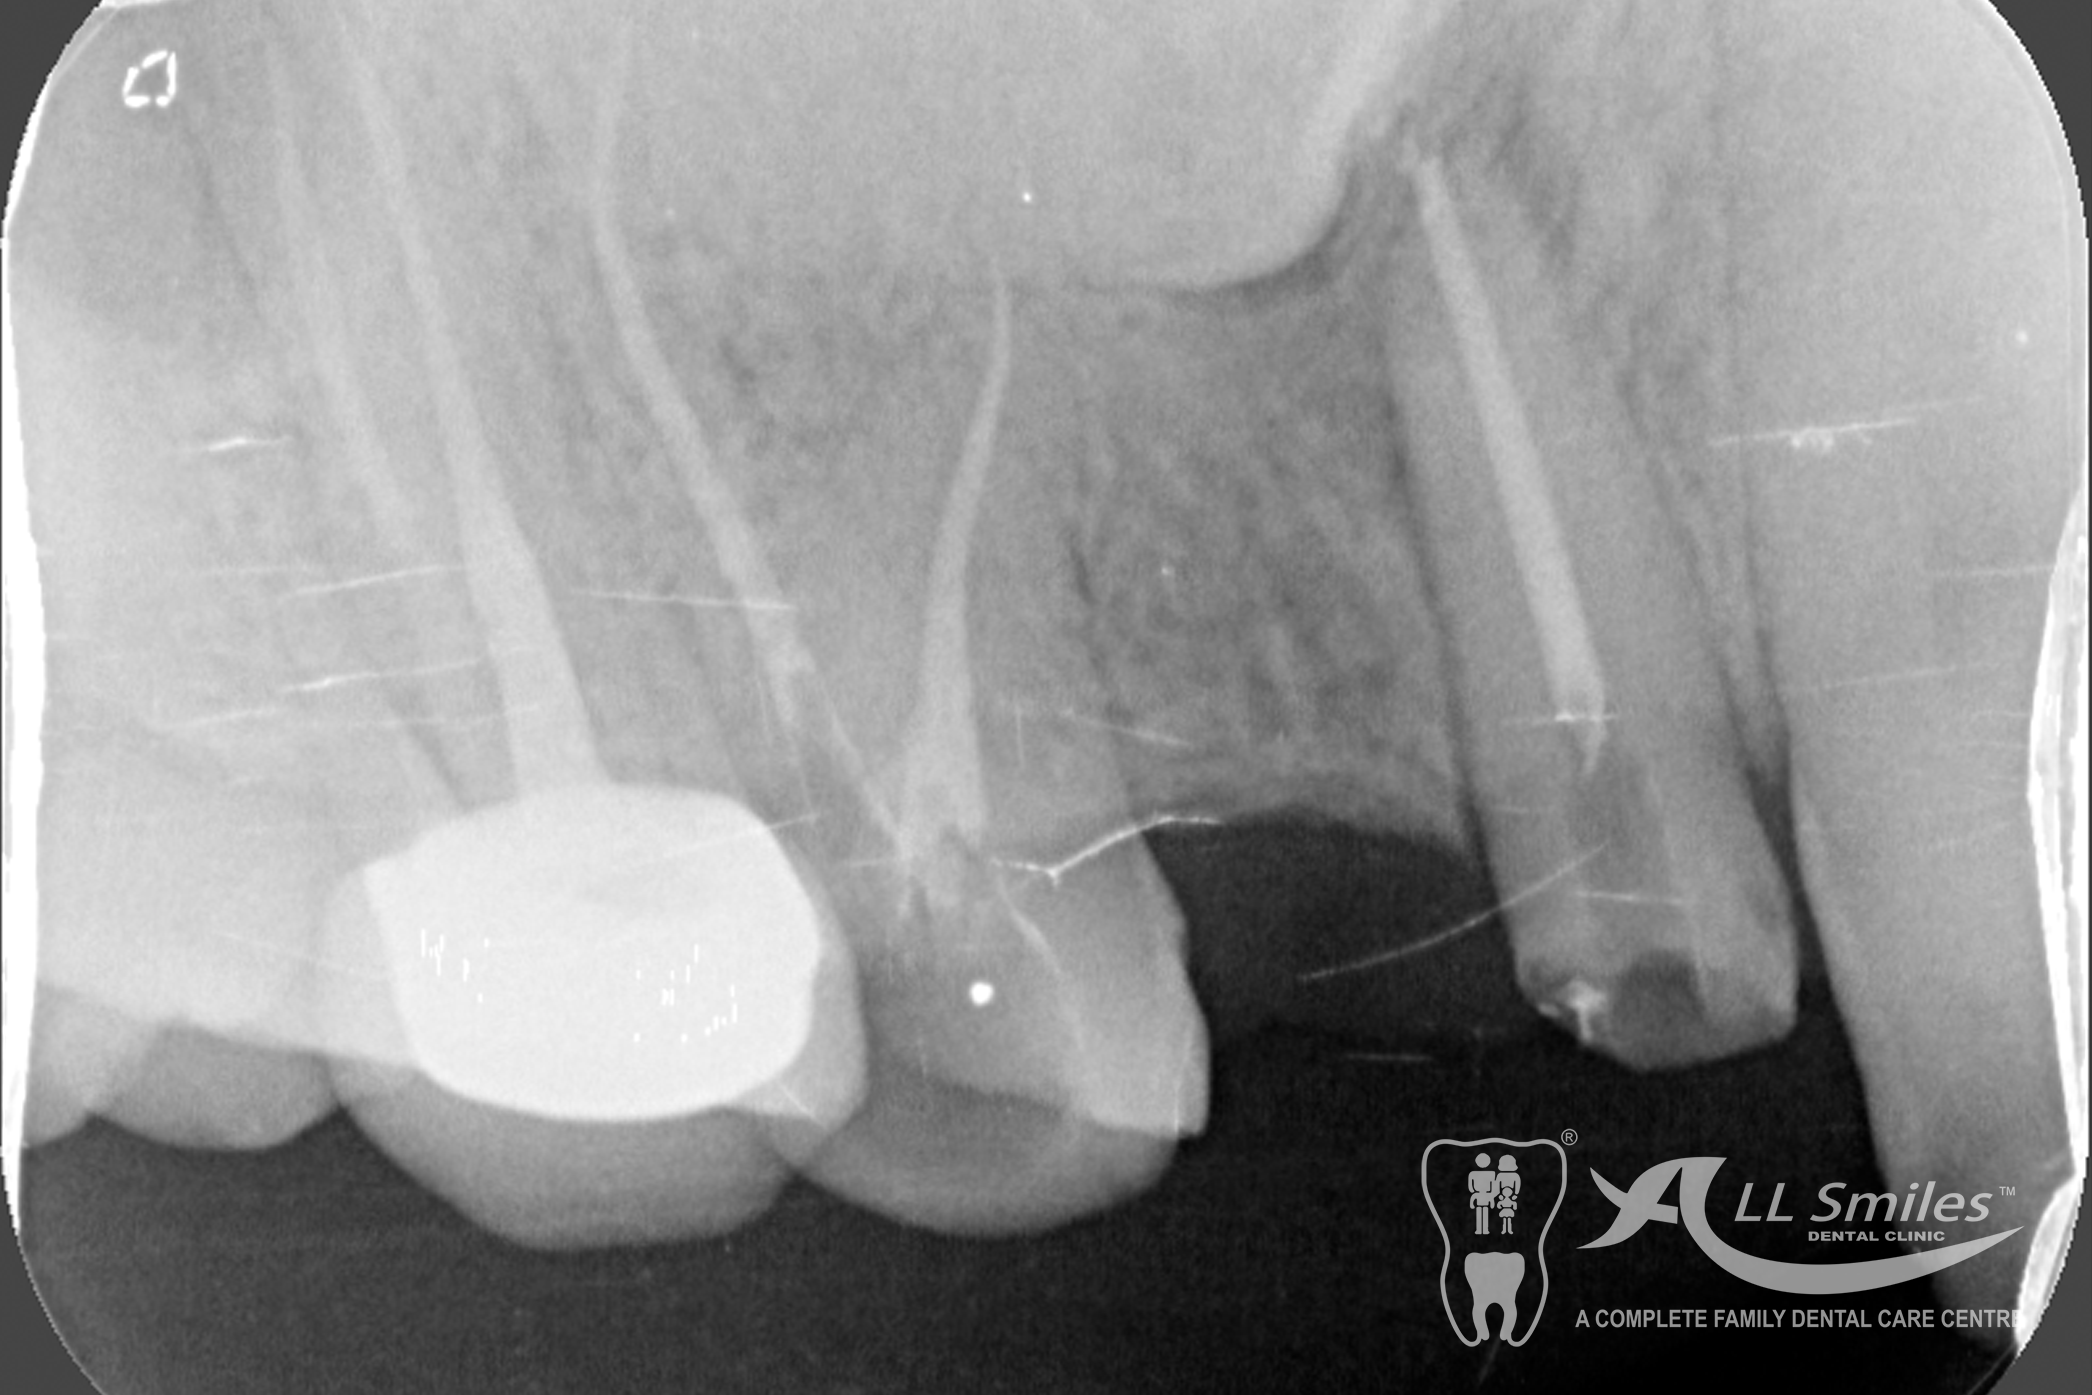

Root Canal Gallery